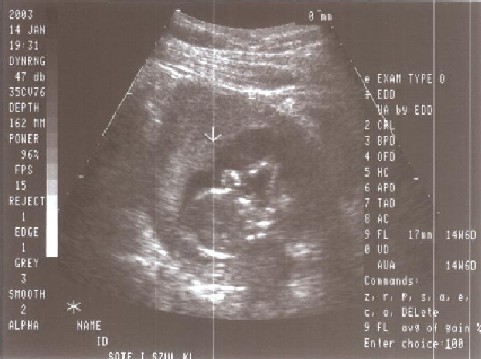

Ez a kép is még anyuci pocakjában készült rólam 2003. április 14-én. Itt profilból látszódom: